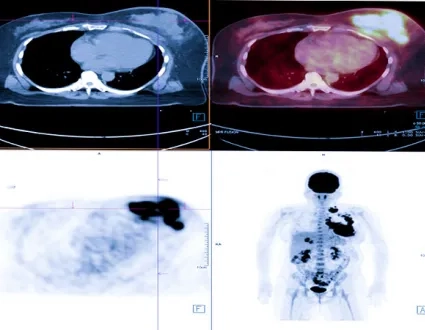

Nuclear Medicine methods are increasingly used in the treatment of cancer, as well as imaging. Targeted atomic therapies have been developing at a stunning pace since 2010.

Theragnostic is a field of medicine that combines patient-specific and disease-targeted diagnosis with treatment. The most important feature of atomic treatments with radionuclides is that the diagnosis can be made with the same drugs, and this provides an extraordinary advantage in cancer treatment. This feature ensures that the drug given for treatment, the area where it will reach in the body, and its effect on the diseased tissue are known precisely before the treatment. This approach is called the “theragnostic” approach.

Unlike conventional chemotherapeutics, theragnostic drugs go directly to the cancer cell, with little or no effect on normal cells. Thus, while healthy cells suffer the least damage, targeted therapy is performed by giving maximum damage to diseased cells such as cancer cells.